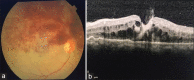

Full-thickness macular hole formation following antivascular endothelial growth factor injection in a case of hemicentral retinal vein occlusion

A rare case reporting the occurrence of full-thickness macular hole (MH) formation following intravitreal antivascular endothelial growth factor injection in a case of hemicentral retinal vein occlusion and the subsequent management of the case. As described in few other similar case reports in the literature, there are quite a few probabilities of factors causing this pathology. An acute posterior vitreous detachment or sudden decompression of the macular edema can quite possibly lead to the above situation. This case report shares light on the evolution of a MH following intravitreal injection and the subsequent treatment process.